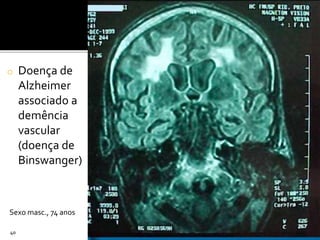

o Doença de

Alzheimer

associado a

demência

vascular

(doença de

Binswanger)

40

Sexo masc., 74 anos